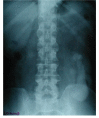

Case presentation: A 51-year male developed incomplete tetraplegia in 1997 when he slipped and fell backwards hitting his head on the floor. X-rays of cervical spine showed fusion at two levels: C2 and C3 vertebrae, and C4 and C5 vertebrae. Intravenous urography (IVU) revealed no kidneys in the renal fossa on both sides, but the presence of crossed, fused renal ectopia in the left ilio-lumbar region. This patient had a similar cervical spinal cord injury about 15 years ago, when he developed transient numbness and paresis of the lower limbs following a fall.